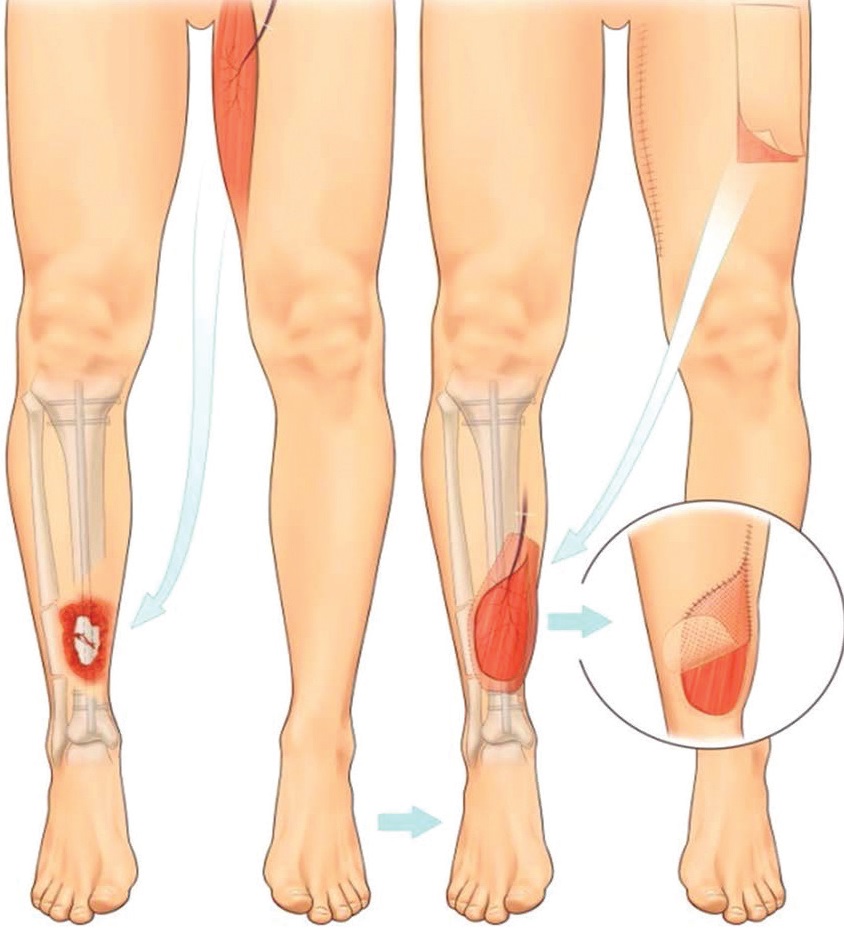

A local flap

This method uses skin next to the wound, which is partially detached and rotated in order to cover the wound. This often creates a secondary skin defect which requires a simple skin graft, this is performed at the same time.

A distant ‘free’ flap

A block of tissue is taken, along with its blood vessels, from a distant part of your body (the donor site) and placed into the wound. This may be in a composite form, which is skin and fat or muscle, or may be just muscle. The blood vessels are then re-attached to the recipient site using microsurgical techniques and the transplanted tissue lives on its new location. The donor site is either stitched closed or may need to be resurfaced with a skin graft. Muscle flaps without skin also require a skin graft on top.

How will my Soft Tissue Reconstruction change over time?

Soft tissue reconstruction, especially involving muscle, always looks bit bulky at start.

However, as the flap matures over time, its volume reduces. It usually levels with the tissue around it but can sometimes remain a bit bulky.

The colour of the flap changes over time to more or less match the skin next to it. The size and colour change is a process that takes time to settle, usually 9-12 months.

The pictures below show a timeline of a muscle flap immediately after the operation (left), after 3 months (right), and after 9 months (bottom).

Very occasionally, any bulkiness that remains can be treated, if necessary, with secondary procedures.